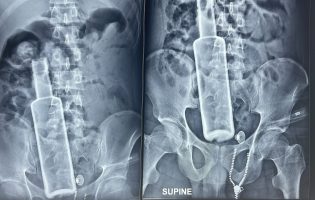

भरतपुरमा बिरामीको पेटभित्र भेटियो रक्सीको सिंगै बोतल